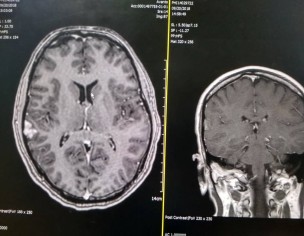

Hello Drs, I am a PhD student and 35 yrs old. My blood pressure raised to 184/124. In my CT-Brain report the doctors concluded that "Extra axial enhancing multilobulated lesion with mild local mass effect. It may represent a meninjoma. Differentials include cavernoma" . The size was observed at right temporal region measuring about 1.2 by 2.1 by 2 cm. Only CT brain has been taken, without any biopsy of brain. Until now, I am not feeling any type of severe pain, except pain in my legs, and my back side. no signs of memory loss, vomiting or severe weakness. but my blood pressure is 140/100. I have conducted heart CT scan as well and it is fully normal. Can anyone suggest me a good neurosurgeon in Pakistan or Malaysia. Currently studying Malaysia but want to come to Pakistan for treatment. Here, In Malaysia Doctors have suggested robotic surgery but because of high cost, I cannot do it in Malaysia.

Attach Photo here: